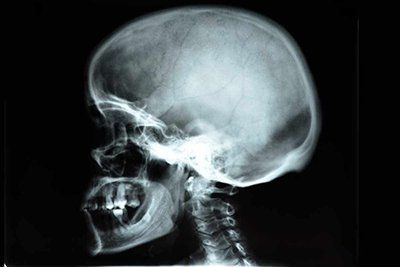

Анатомия носовой полости достаточно сложна и предусматривает наличие различных костных образований. Сам нос выполняет ряд жизненно важных для любого человека функций, поэтому любые повреждения его костной системы могут стать причиной опасных для жизни состояний. Рентген костей носа позволяет наличие чужеродных тел в полости, выявить новообразования любой природы, определить последствия травм и различные патологические состояния.

Это — диагностическая методика, которая позволяет лечащему врачу получить информацию о состоянии костных структур носа, выявить признаки развития заболеваний и правильно поставить диагноз. Она является абсолютно безболезненной и не требует много времени, её широкая распространённость делает её доступной для любого пациента. Сделать рентген костей носа можно в многопрофильной клинике ЦЭЛТ. Мы практикуем индивидуальный подход и сервис в соответствии с международными стандартами, поэтому Вы получите услуги высокого профессионального уровня.

Что видно на рентгене костей носа в норме?

Снимок рентгена костей носа в норме визуализирует:

• Костные структуры;

• Лобные и гайморовы пазухи;

• Ячейки височных костей;

• Решетчатые пазухи (в определённой проекции);

• Околоносовую пазуху.

Здоровые костные структуры имеют чёткие очертания и тонкие стенки, носовые пазухи имеют идентичную пневматизацию, а ячейки решётчатой кости хорошо просматриваются.